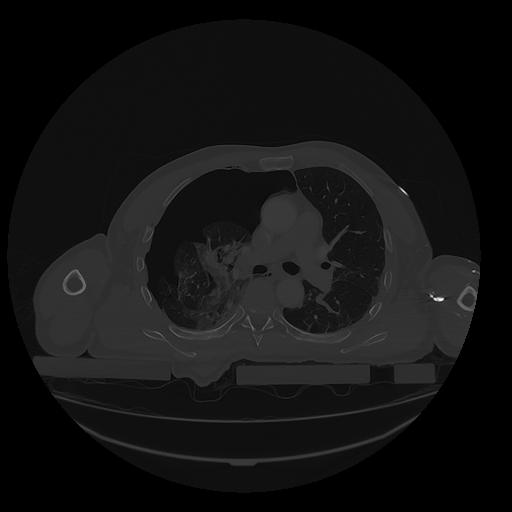

31 PULMON,CE,Vol,1.0,PULMON,,